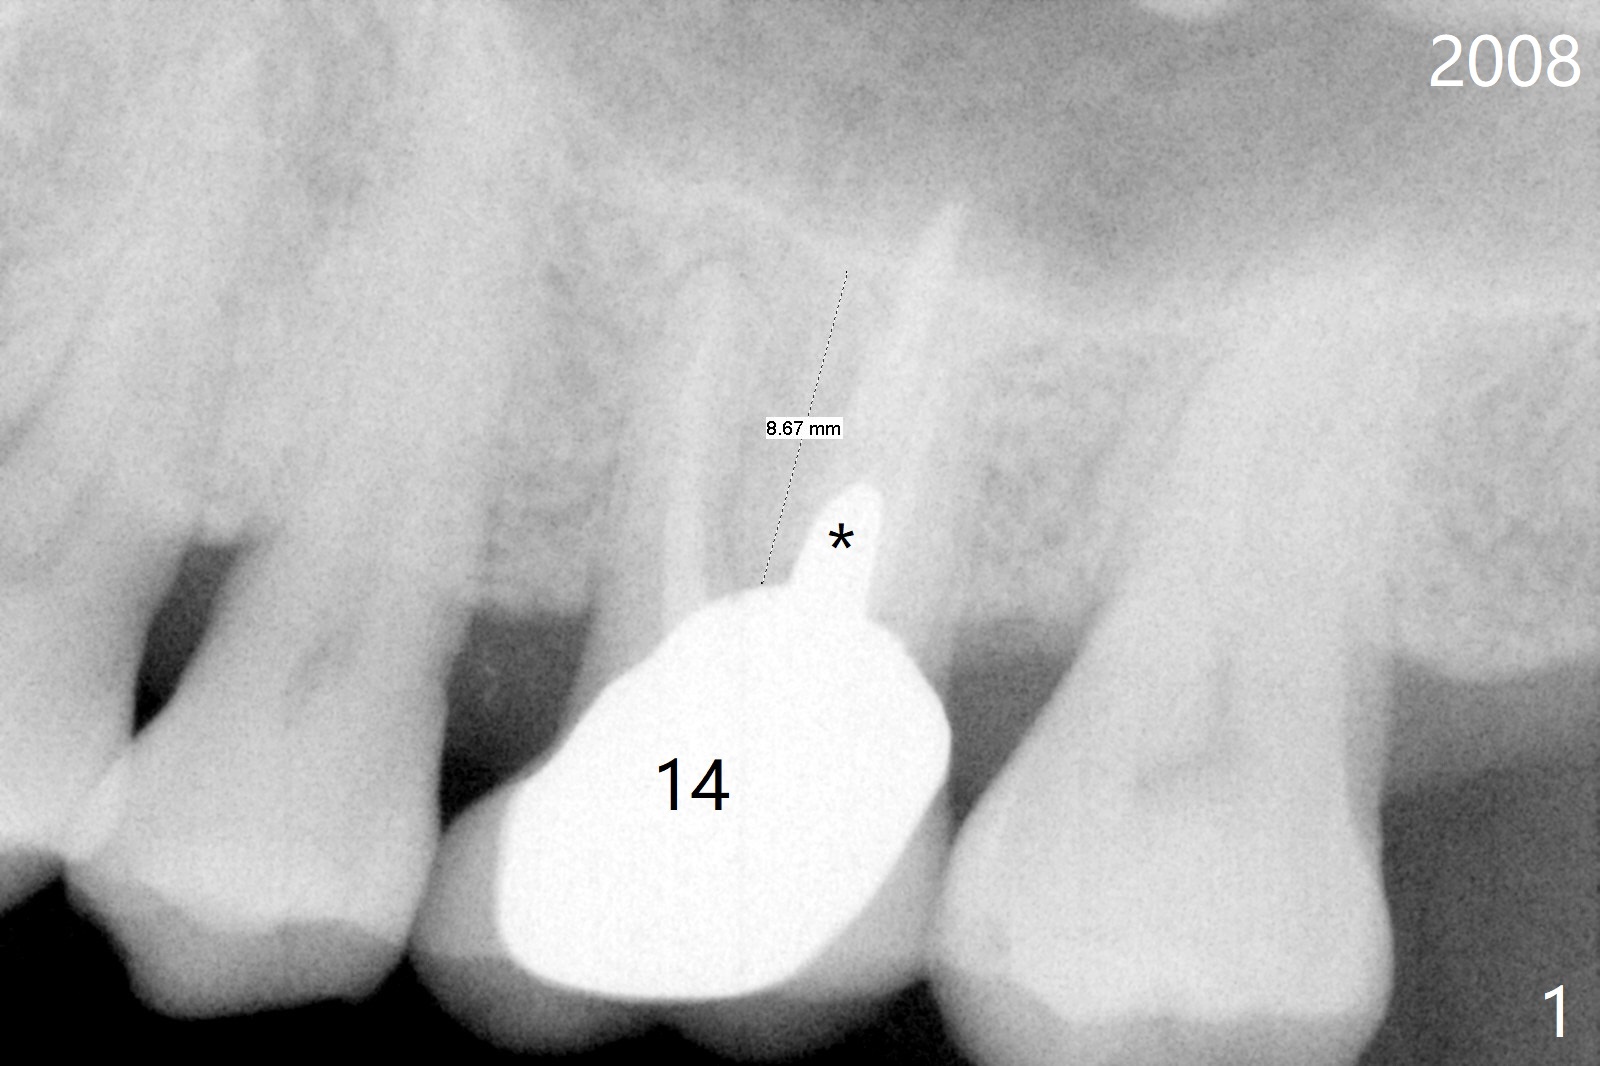

A 64-year-old man will return for #14 extraction/implant due to palatal root fracture (Fig.1,2). He has a history of cheek bite when the teeth #1-3 are replaced by implant crowns. His models for these crowns have been found. Alginate impression has been taken for the arches so that the new crown will be fabricated as close as possible to his original one. Take preop photos to show palatal root fracture and overjet buccally. Initiate osteotomy in the septum slightly buccally due to the palatal bone defect; the depth will be 8.5 mm (Fig.1,2). Use DIO Bone Expanders or an implant to break the sinus floor (Fig.3). The implant will be placed slightly apical to the crest.